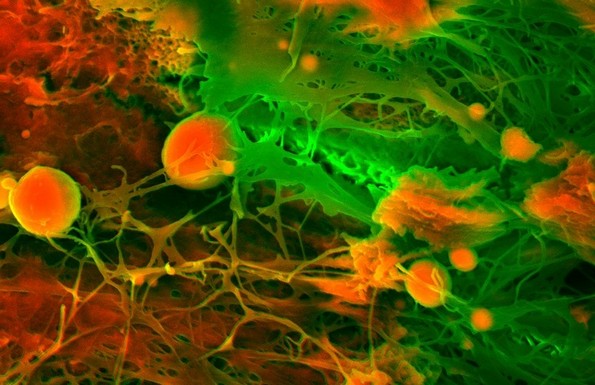

4. Срце